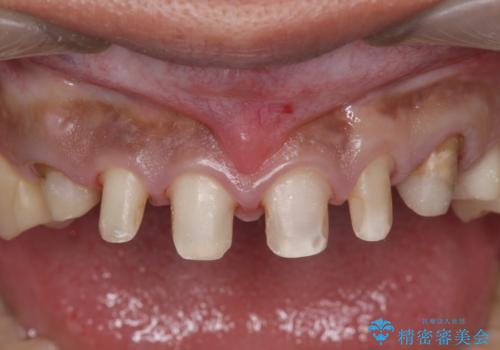

複数箇所コンポジット充填された前歯をセラミック治療

- コンポジットレジンの充填箇所がすり減ってしまい、形の悪くなった前歯の治療を希望され来院されました。

充填部位が大きく、再度充填をするには神経と近くなり抜髄のリスクが高まるため、劣化の少ないセラミックでフルカバーするセラミッククラウン治療を行うこととしました。

- 79.2万円(ジルコニアクラウン×6・仮歯×6)費用は治療当時の料金となります